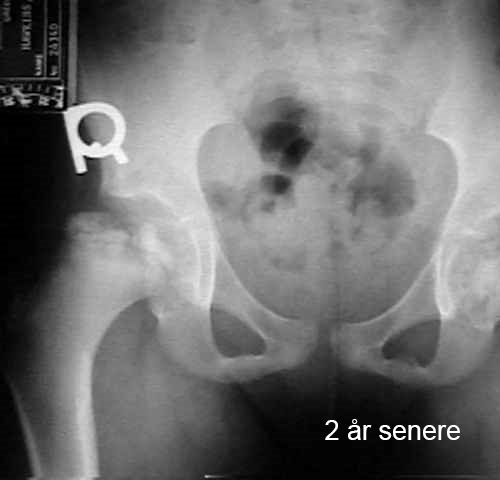

Lårbeinshodet dør delvis eller helt. Kroppen forsøker å løse dette ved å danne nytt beinvev og bryte ned det døde vevet. Det nye beinet er fortsatt svakt, noe som kan føre til at hoften mister sin runde form eller kollapser. Dette fører til deformasjon av hofteleddet. Bildene viser utviklingen av hoften hos et barn med Calvé-Legg-Perthes sykdom.